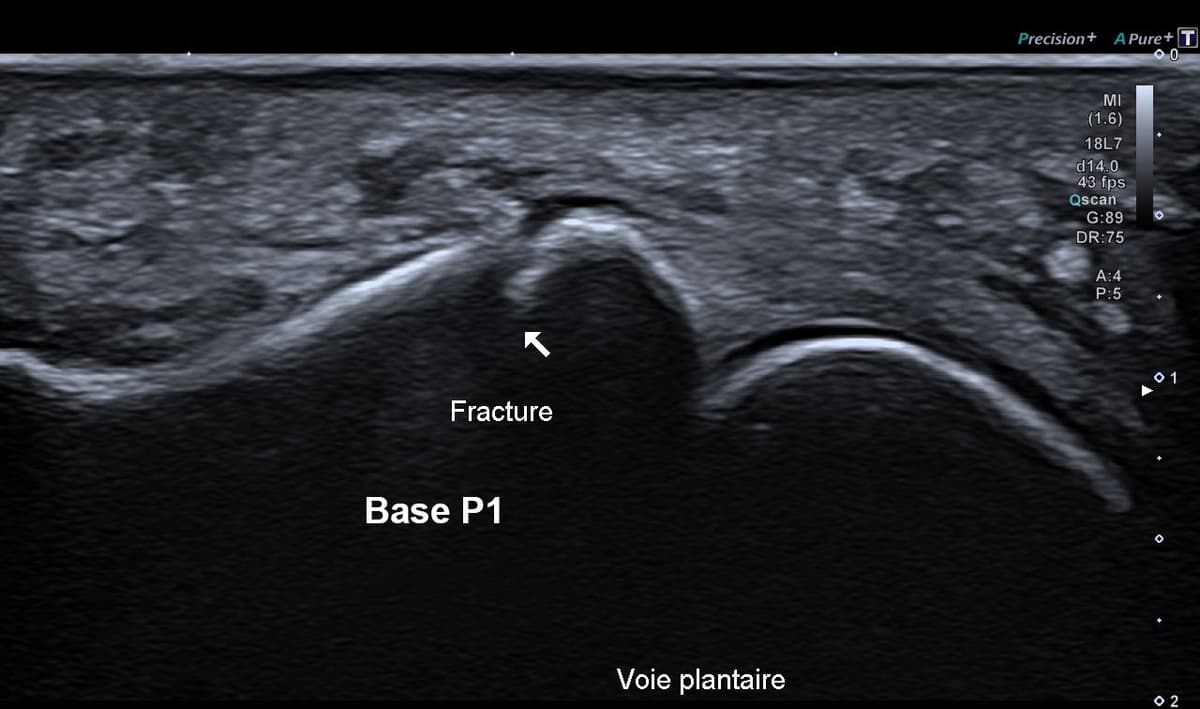

Fracture phalangienne d'un orteil

Fracture instable étudiée en échographie dynamique

US